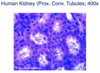

Identify:

Simple cuboidal epithelium.

* Photomicrograph of kidney tubules

Simple cuboidal epithelium

Simple cuboidal

Simple cuboidal